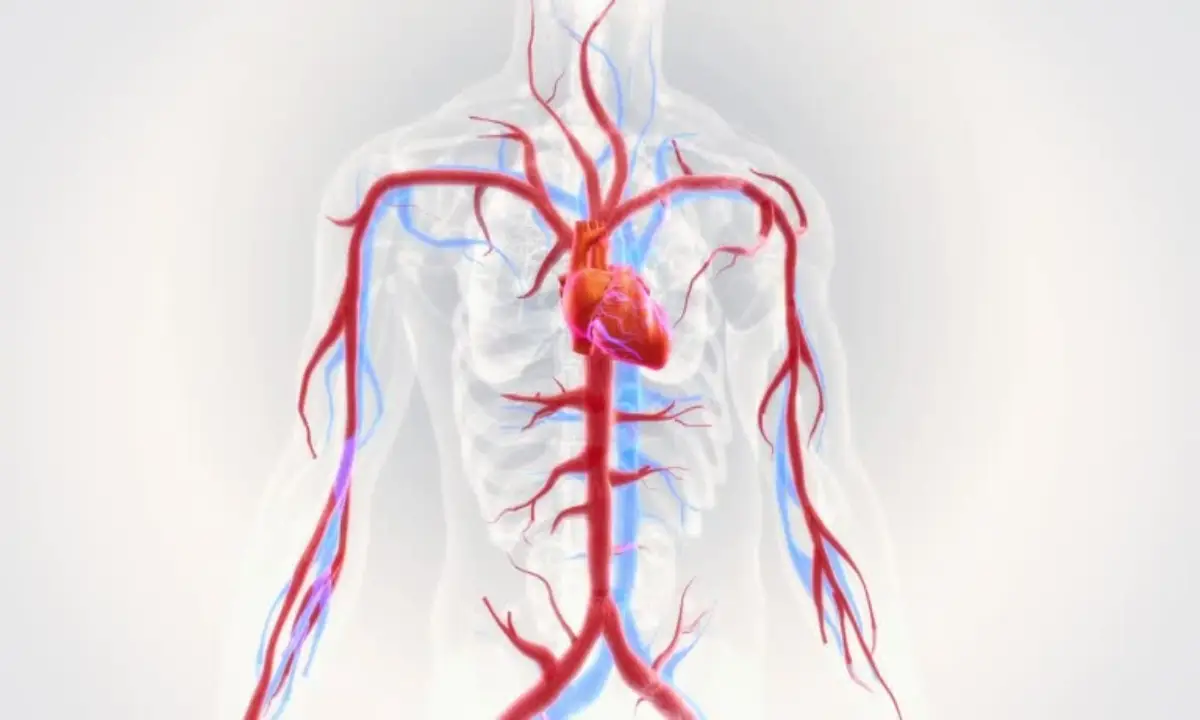

ماهیچه قلب یا میوکارد، مسئولیت پمپاژ خون به سراسر بدن را بر عهده دارد، وظیفهای که به مقادیر زیادی انرژی و اکسیژن نیاز دارد. این نیاز حیاتی توسط شریانهای کرونری تأمین میشود. این سرخرگها از قاعده آئورت، بزرگسرخرگی که خون غنی از اکسیژن را از بطن چپ خارج میکند، منشعب میشوند. یک ویژگی فیزیولوژیکی منحصربهفرد در مورد این شریانها آن است که برخلاف سایر نقاط بدن که خونرسانی در فاز انقباض (سیستول) به اوج خود میرسد، بیشترین جریان خون به میوکارد در فاز استراحت قلب (دیاستول) رخ میدهد. این پدیده به این دلیل است که در طول انقباض، فشار ناشی از ماهیچههای قلب، عروق کرونری را فشرده کرده و جریان خون را کاهش میدهد، اما در فاز استراحت، رگها باز شده و خون به راحتی به بافت قلب میرسد. همین وابستگی حیاتی به جریان خون دیاستولیک، قلب را به شدت در برابر هرگونه انسداد در این شریانها آسیبپذیر میسازد.

سرخرگ کرونری چپ (LCA) از قاعده آئورت خارج میشود و به سرعت به دو شاخه اصلی تقسیم میگردد. این شاخهها مسئول تأمین خون بخش عمدهای از ماهیچه قلب، بهویژه بطن چپ که ضخیمترین و پرکارترین حفره قلبی است، هستند.

شاخه دوم سرخرگ کرونری چپ، سرخرگ سیرکومفلکس (LCx) است که در امتداد شیار کرونری (شیار دهلیزی-بطنی) به سمت چپ قلب میرود. این سرخرگ خود به شاخههای کوچکتری مانند سرخرگ حاشیهای چپ (Left Marginal) و سرخرگ بطنی خلفی چپ (Posterior Left Ventricular) تقسیم میشود. این شاخهها مسئول تأمین خون بخشهای خلفی و جانبی بطن چپ هستند. مسیر این سرخرگ و شاخههای آن، تضمین میکند که بخشهای مهم و بزرگ ماهیچه قلب، حتی از نواحی دورتر نیز به خوبی خونرسانی شوند.

سرخرگ کرونری راست (RCA) از سمت راست آئورت منشعب میشود و در شیار کرونری به سمت راست حرکت میکند. این سرخرگ وظیفه تأمین خون دهلیز راست، بطن راست و دو سوم خلفی سپتوم بین بطنی را بر عهده دارد. مسیر آن به سمت مرز قدامی قلب ادامه مییابد و شاخههایی مانند سرخرگ حاشیهای راست (Right Marginal Artery) را از خود جدا میکند. این شاخه در امتداد مرز قدامی-تحتانی قلب حرکت کرده و به بطن راست خون میرساند.